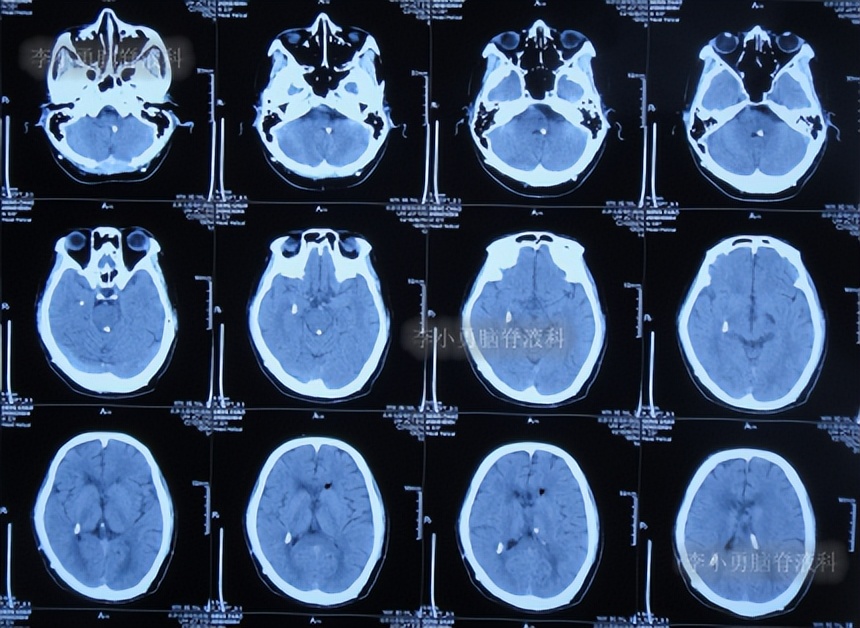

2022年4月28日(住院治疗193天)出院,出院时:意识清楚,言语交流正常,肢体活动、走路基本正常(图-50);查头颅CT示未见异常(图-51)。

图-50:2022年4月28日出院时

图-51:出院时头颅T